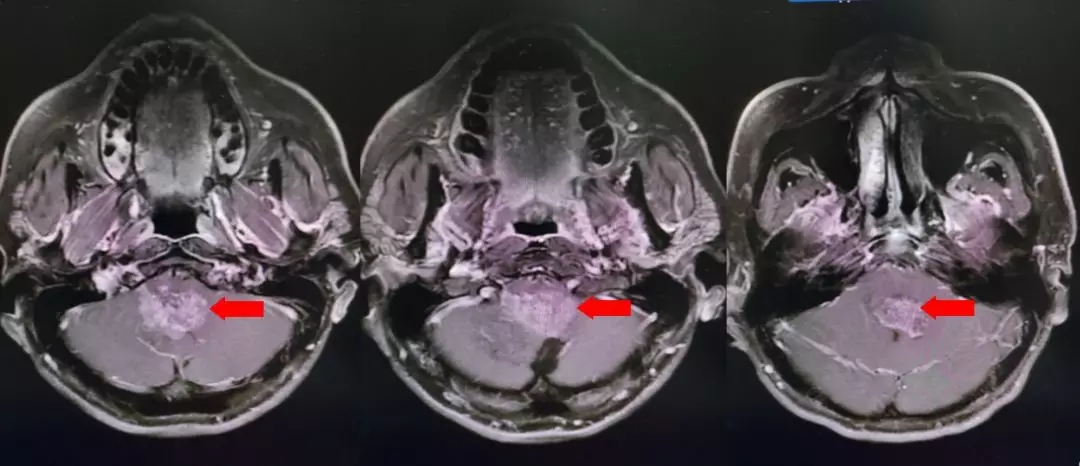

颅脑核磁增强扫描

颅脑核磁平扫加增强扫描:

第四脑室内见一巨大形态不规则的异常信号影,肿瘤信号不均匀,T1W1呈略低信号影,T2W1呈稍高及高信号影,增强扫描可见肿瘤不均匀明显强化。肿瘤充满整个四脑室,大小约44*37*55mm,上方接近四脑室顶部,下方至颈2脊髓平面上方,已经部分侵袭桥脑、延髓,局部边界不清,无明显间隙,脑干局部明显受压变形。肿瘤上方脑室系统扩张,出现梗阻性脑积水征象。

影像诊断:1.第四脑室内占位性病变,室管膜瘤可能性大;2.梗阻性脑积水。